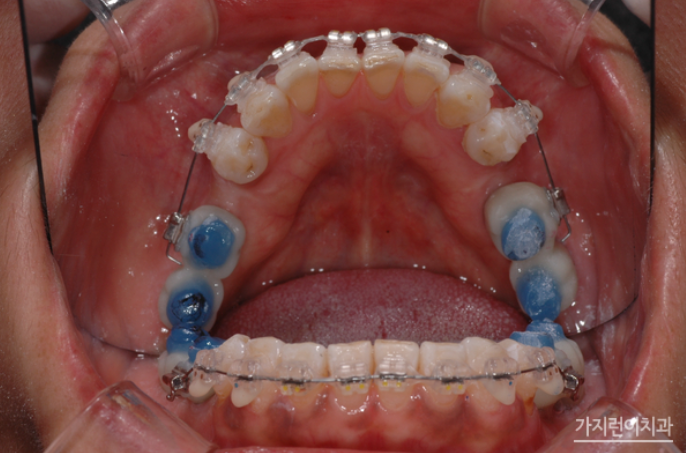

이후 치료가 시작된 지 1년이 지났고 상악 작은 어금니를 발치해 안정적인 교정을 진행하셨는데요. 안정적인 교정을 위해 상악 설측교정 장치는 두개의 와이어를 사용하는 탄댐설측교정 장치로 진행했습니다.